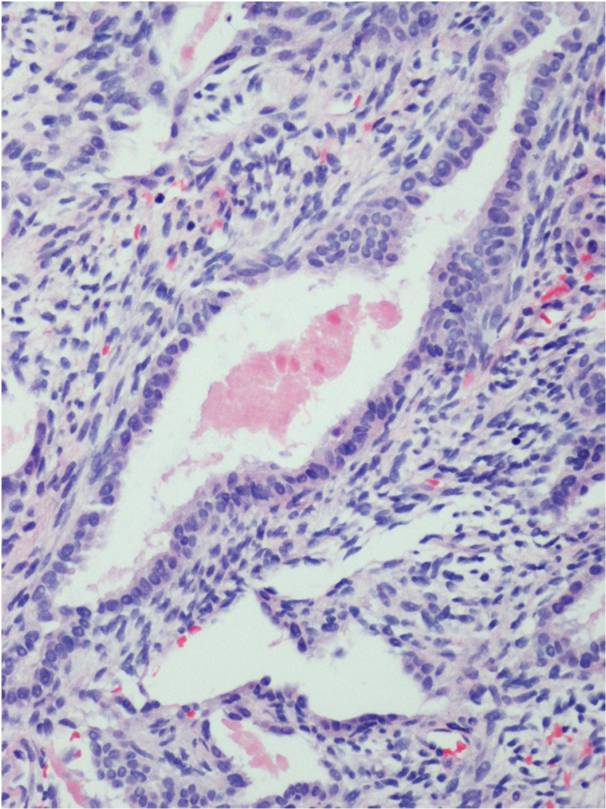

Microscopic Pathology

Synovial Sarcoma is composed of two different cell types

Spindle cell (small, uniform, and ovoid cells with pale nuclei and the cytoplasm is sparse)

Epitheloid cell (ovoid nuclei and abundant cytoplasm)

Biphasic form is composed of both epithelial-cell and spindle-cell components in equal proportions (Fig. 6-8)

Monophasic Fibrous type predominantly spindle cell.

Monophasic Epithelial type is difficult to differentiate from adenocarcinoma without cytogenetics and immunohistochemistry.

Poorly differentiated type demonstrates features of high grade small round cell tumor with dense cellularity, numerous mitotic figures, and areas of necrosis.

Inmunohistochemical profile: Vimentin (+), Cytokeratin (+), Epithelial Membrane Antigen EMA (+)